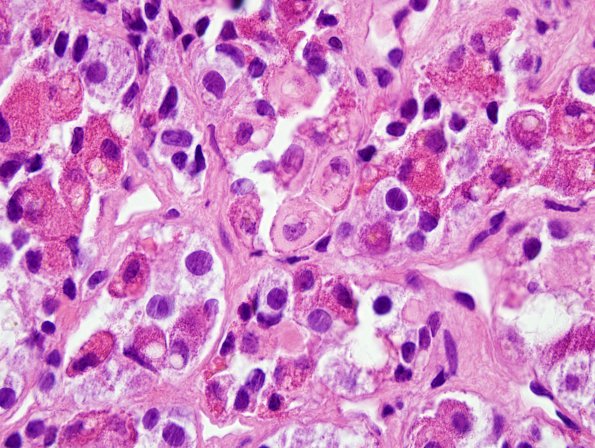

Washington University Experience | NEOPLASM (SELLAR) | Pituitary Adenoma - Pituitary Neuroendocrine Neoplasm | Corticotroph | 16A5 PA, CR (Case 16) H&E 5.jpg

These images of the non-tumorous acini show prominent Crooke’s hyaline change. (H&E)